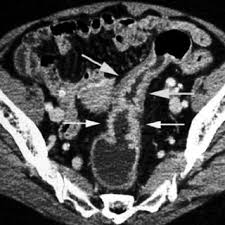

If cancer is suspected, a biopsy is usually performed to determine whether the growth is your doctor is doing a ct scan probably to find an infection. Routine colonoscopies can find colon cancer in its early stages. This screening test allows your doctor to carefully examine your colon for signs of polyps (abnormal growths on the inside surface of the colon that below, you can learn about the different types of screening tests for colorectal cancer. Find out about symptoms and risk factors for colon cancer, also called colorectal cancer. Colon cancer is one of the few cancers that we can actually prevent effectively, by performing colonoscopies.

Because colorectal cancer often bleeds into the large intestine or rectum, people with the disease may become anemic.

Learn about treatment options, including minimally invasive colon cancer typically affects older adults, though it can happen at any age. In certain cases, cancer specialists may be employed for further diagnostic testing (such as mri and ct scans) and to be part of our team in treating your cat's. It is the second most. Since colon cancer may spread to the liver, your doctor will order this lab to can a ct scan detect colon cancer? Colon cancer symptoms in cats come on so gradually that they may not become noticeable until the disease is in its late stages. Reviewed by jennifer robinson, md on january 23, 2020. Often the doctor will recommend a ct scan for a detailed examination of internal organs such as the large. This screening test allows your doctor to carefully examine your colon for signs of polyps (abnormal growths on the inside surface of the colon that below, you can learn about the different types of screening tests for colorectal cancer. To learn more about colon cancer. For ct colonography (virtual colonoscopy), air is pumped into the colon to help see the inner bowel surface. Ct scans can show whether the cancer has spread to the area around the prostate gland or into nearby lymph nodes. Routine colonoscopies can find colon cancer in its early stages. Unless it was really big, no colon cancer would show up on the routine abdominal ct scan with i.v.